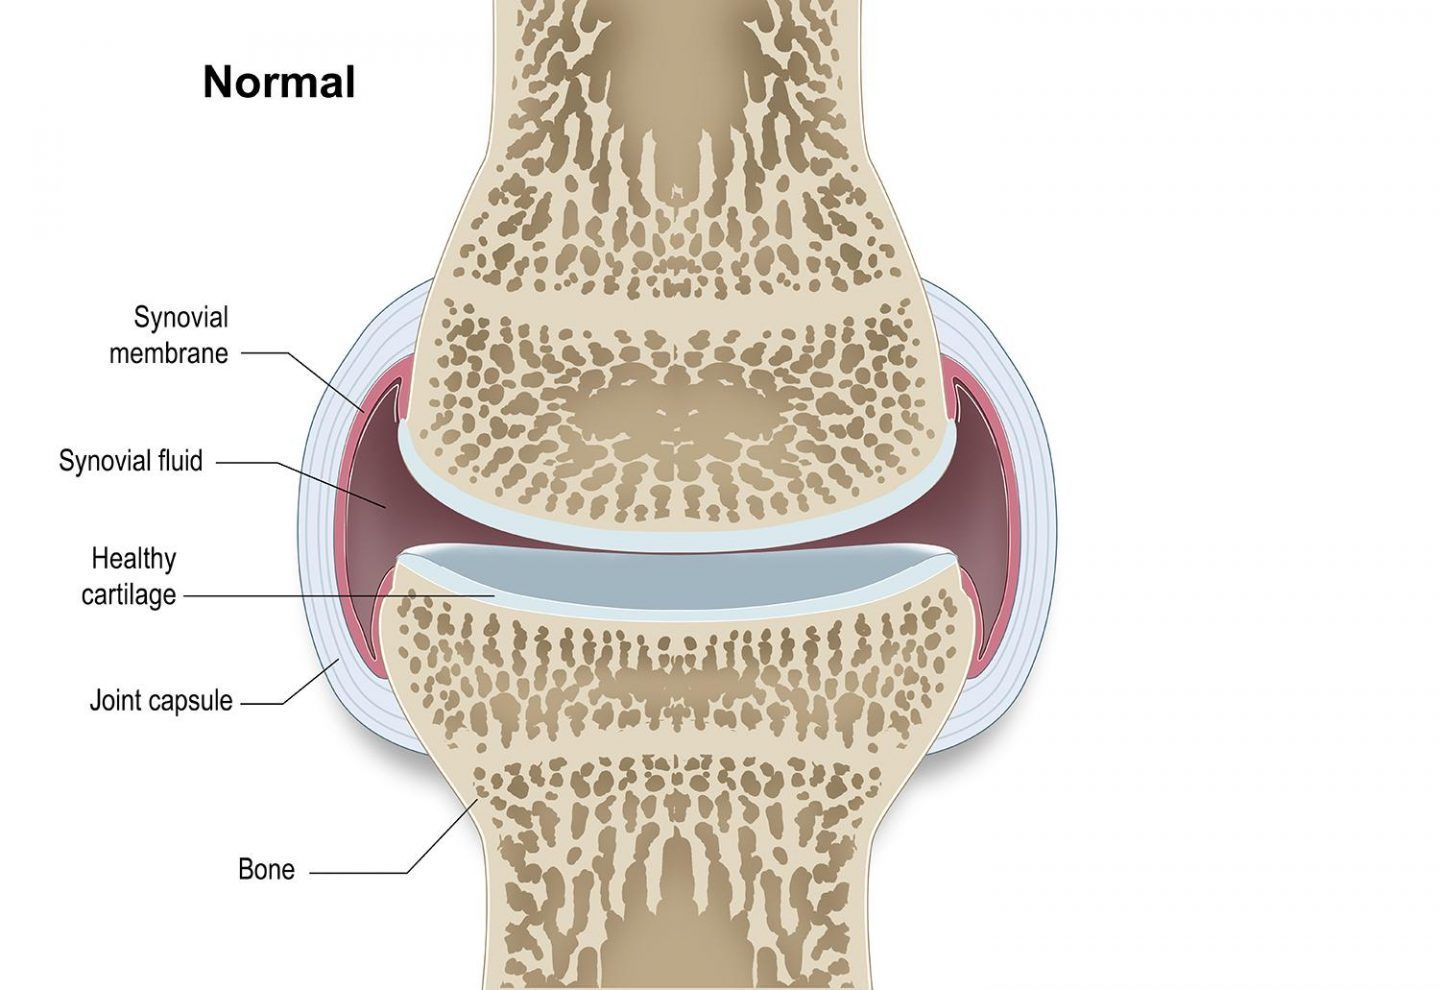

Diagnosing OA Canine Arthritis Resources and Education Canine Arthritis Resources And Education arthritis in dogs | canine arthritis resources & education. learn how to identify, assess, and treat canine osteoarthritis (oa) with a multimodal approach that includes weight loss, nsaids, physical rehabilitation, and more. osteoarthritis is a common problem in dogs, particularly in seniors and large breeds. canine arthritis resources and education (care) is dedicated to helping veterinarians. Canine Arthritis Resources And Education.